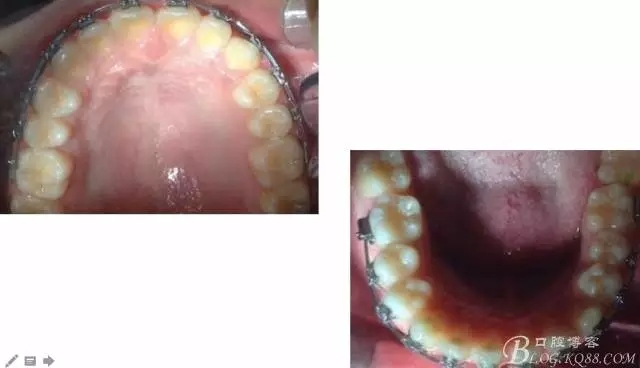

中線不齊,咋辦?繼續(xù)哄哄患者配合,2牽+斜牽。

努力沒有白費,中線基本對齊!